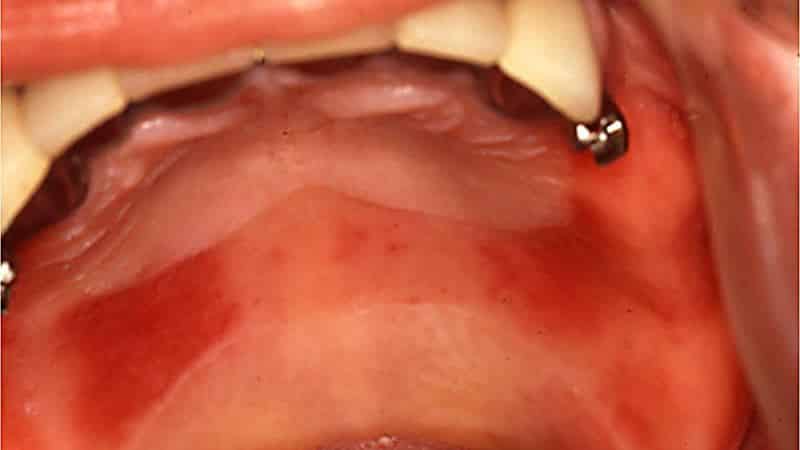

- При установке металлических конструкций в ротовой полости часто происходят изменения в внутренней среде;

> Если вы подозреваете наличие злокачественной опухоли на небе, обязательно обратитесь к врачу. - Часто слизистая страдает при использовании протезов. При этом, чем дольше носится конструкция, тем выше риск развития патологического процесса, который может проявляться по-разному.